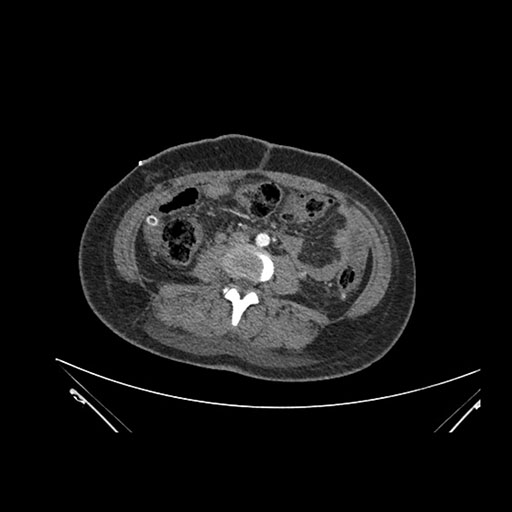

Imaging Analysis

Look through the patient's CT scan to identify any areas of concern for the necessary procedure.

Axial Arterial

Based on initial findings, which issue(s) would you be most concerned about?